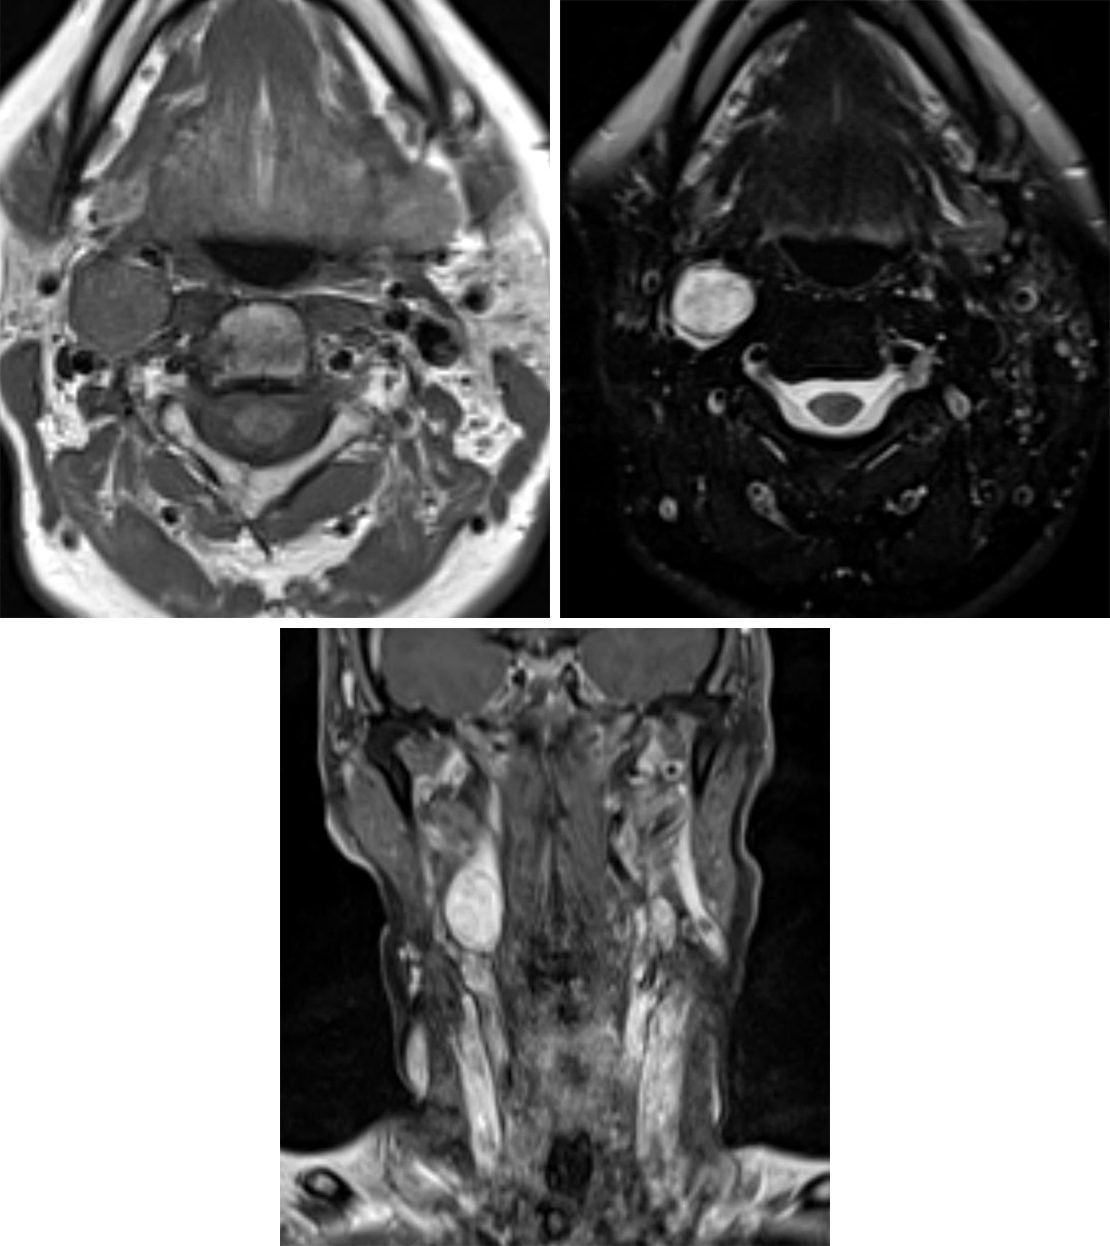

• Magnetic Resonance Angiography (MRA): Utilizes magnetic fields to visualize the vessels.